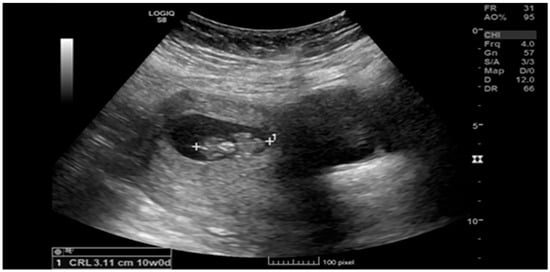

Ruptured Heterotopic Pregnancy: Laparoscopic Management, Preserving Intrauterine Viability

Pregnancy (HP), defined as the coexistence of intrauterine and ectopic gestations, is a rare condition, especially in spontaneous conception, but it is a life-threatening obstetric emergency when rupture occurs, with a reported maternal mortality rate of 0.03%. Diagnosis is often delayed because confirmation of an intrauterine pregnancy can mask clinical signs of a concurrent ectopic gestation. Early recognition and prompt surgical intervention are therefore critical to maternal safety and preservation of intrauterine viability. This case highlights the diagnostic challenges and successful management of a spontaneous ruptured heterotopic pregnancy. Case presentation: A 34-year-old Middle Eastern woman, gravida 4, with a spontaneous conception, presented with sudden severe lower abdominal pain and signs of acute hemoperitoneum (hypotension, tachycardia, and marked peritoneal signs). Transvaginal ultrasound demonstrated a viable intrauterine pregnancy at 9 weeks 4 days gestation, together with a ruptured left tubal ectopic pregnancy of similar gestational age. The patient underwent urgent laparoscopic left salpingectomy with evacuation of approximately 1200 mL of intraperitoneal blood and clots. Postoperatively, she developed significant anemia (hemoglobin drop from 11.2 g/dL on admission to 6.5 g/dL) requiring transfusion of four units of packed red blood cells. Serial ultrasonographic follow-up confirmed ongoing viability of the intrauterine pregnancy, which ultimately resulted in a live birth at term. Progressive resolution of the postoperative pelvic hematoma was also noted. Conclusions: Ruptured heterotopic pregnancy remains a diagnostic and therapeutic challenge. This case, along with a synthesis of the contemporary literature, demonstrates that a high clinical index of suspicion, timely ultrasound diagnosis, and immediate minimally invasive surgical management are paramount. Furthermore, rigorous postoperative monitoring and resuscitation, including targeted transfusion, are essential to achieve maternal stabilization while allowing continuation of a viable intrauterine pregnancy, with reported live birth rates exceeding 70% following timely intervention. Full article